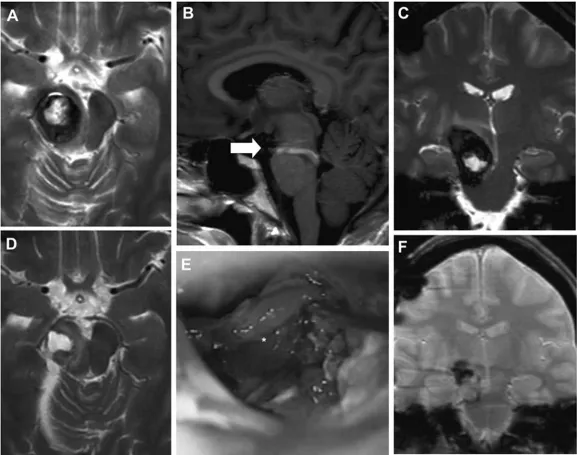

图2:患者1分娩后的术前MRI(A–C)、术中视图(D)和术后MRI(E和F):轴向(A)、矢状面(B)和冠状面(C)MRI平面显示脑干海绵状血管瘤病变的残余和较大的DVA(箭头,B)。术中显微镜观察(D)显示手术腔和海绵状血管瘤残留(星号)。